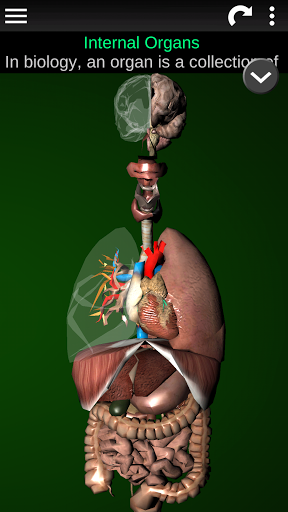

Показує 3D анатомічну модель основні органи людського тіла та опис кожного з них.

* Травна система, включаючи шлунок, тонку кишку, товсту кишку та анімацію цієї системи.

* Дихальна система, яка включає трахею, бронхи, легені та анімацію цієї системи.

* Мозок, який включає головний мозок, мозочок і стовбур мозку.

* Серце, що включає передсердя, шлуночки, аорту і одушевлення цього органу.

* Легкий доступ і навігація (масштабування, 3D-обертання).

* Приховати або показати інформацію.